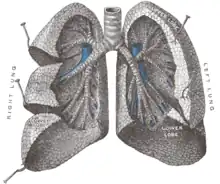

Segmentation pulmonaire

Le poumon droit est divisé en trois lobes (supérieur, moyen et inférieur), le gauche divisé en deux (supérieur et inférieur). À gauche, la partie lingulaire du lobe supérieur correspond au lobe moyen droit, tandis que la partie culminale (culmen) correspond au lobe supérieur droit. Les lobes sont séparés par des scissures, deux à droite (la grande ou « oblique », et la petite ou « horizontale ») et une à gauche (l'oblique).